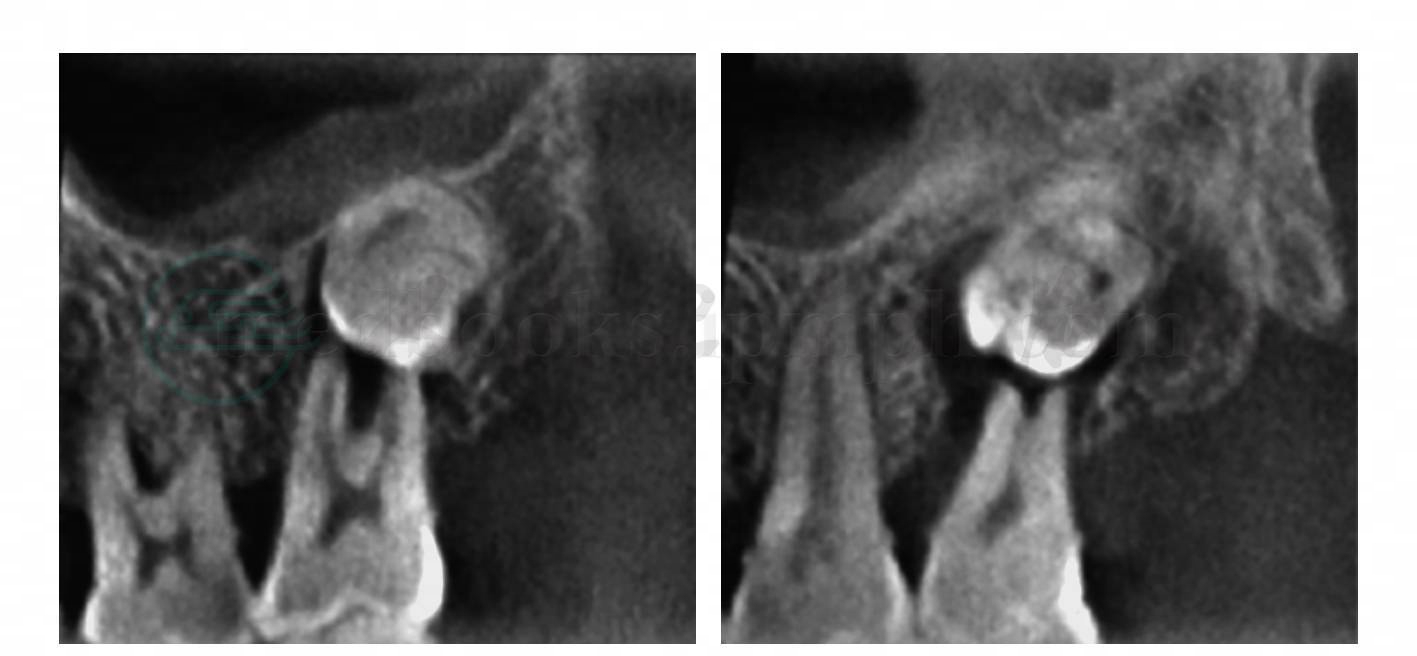

图2 上颌阻生智牙

不同层面的斜矢状位观察可见第二磨牙的腭根压迫吸收